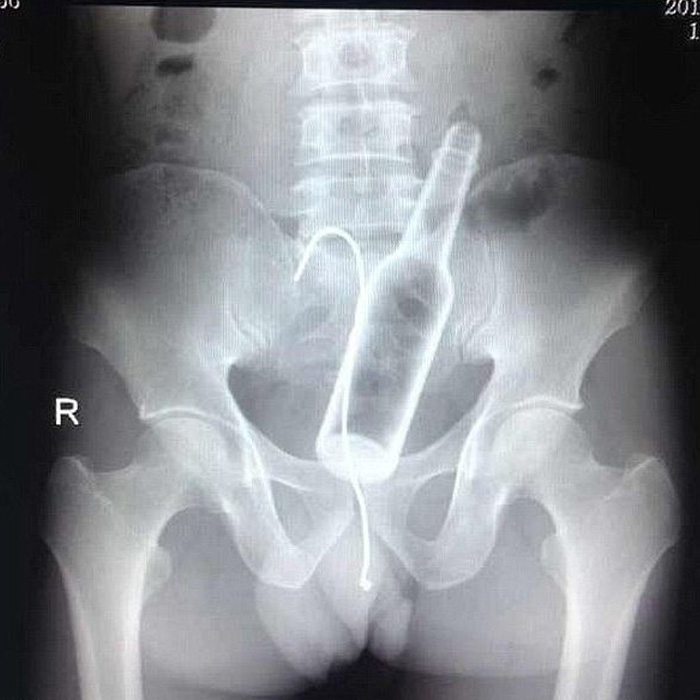

Yeah you know, personal inventory and accountability just don’t ever really get that far derailed. I see cop shows very often and as soon as toads get caught with dope in their car they swear it isn’t theirs. They claim to have had people in and out of their car all day so it must belong to one of them. This is marginally believable, but in this case, we are talking about a bodily cavity:

“Gosh, officer… there have been so many people running in and out of there all day, any one of them could have dropped the meth there in their mad dash to get back to the office!”

It is never essential (to me) for you all to believe me, but I saw the male version of this story on AE Live PD on YouTube last-freakin-night! I jumped back in my browser just about 10 windows and found it! Check this out before we conclude.

Ladies and gentlemen, I implore you! The cop is correct and I did some modest research on my own online in the realm of women’s apparel, and this is what I found:

So there it is, all laid out dress-right-dress for you all. There is no denying knowledge of crank dubs discovered in your body cavities. The day that plea will ever bode well in court is the day that monkeys will fly out of my ass — how the hell did those get up there??